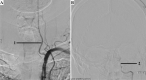

The A.N. Kazantsev artery is a vessel starting from the common carotid artery with subsequent bifurcation into 2 vessels of equal size-the internal carotid artery (ICA) and the persistent embryonic hypoglossal artery (PEHA). Until now, this artery has been considered as the ICA. However, according to all existing classifications, the ICA in the cervical segment does not have arterial branches. In addition, in view of the comparable sizes of PEHA and ICA, PEHA itself cannot be considered a branch of the ICA. Thus, by the right of the first description, the authors of the article named this vascular formation as the A.N. Kazantsev artery, which forms a bifurcation of the PEHA and ICA. In this clinical case, carotid angioplasty (CAS) was performed with stenting of 80% stenosis of the A.N. Kazantsev artery in the most acute period of acute cerebrovascular accident (ACV). According to angiography, the following was also revealed: the presence of PEHA, extending from the A.N. Kazantsev artery 5 cm above its mouth, connecting with the main artery; stenosis of the right vertebral artery 60% at the mouth; hypoplastic left vertebral artery with aplasia of the V4 segment; open circle of Willis (VC): absence of both posterior communicating arteries (PCA). Due to the high risk of recurrent CVA due to clamping of the A.N. Kazantsev artery during CEA, a multidisciplinary consultation decided to implement an emergency CAS of the A.N. Kazantsev artery. The distal embolism protection system FilterWire was inserted into the proximal part of the basilar artery through the radial artery on the left. The distal embolism protection system RX Accunet was inserted into the distal parts of the left ICA through the left common femoral artery. According to Seldinger, an Acculink stent 7-10 × 30 mm was inserted into the affected area of the A.N. Kazantsev artery, positioned and opened. The postoperative period was uneventful. ACV did not recur. Conducted dual antiplatelet therapy (acetylsalicylic acid 125 mg in the afternoon + clopidogrel 75 mg in the morning). The patient was discharged from the institution on the 10th day after the operation in a satisfactory condition.